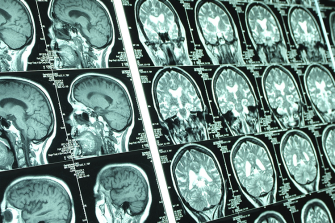

Based at the Centre for Healthy Brain Ageing (CHeBA), UNSW Sydney, the Neuroimaging Laboratory (NiL) is dedicated to advancing our understanding of how and why the brain changes with age. Our overarching objective is to use state-of-the-art neuroimaging techniques to identify clinical, lifestyle, genetic, and environmental determinants of brain ageing in both healthy older adults and those with dementia. By integrating brain scans with rich medical and lifestyle data, we investigate factors that support healthy brain ageing or, conversely, contribute to brain disease. This knowledge is critical for developing strategies to maintain brain health and potentially delay or prevent conditions such as Alzheimer’s disease.

Our primary imaging modality is Magnetic Resonance Imaging (MRI), which provides high-resolution insights into brain structure and function. We also incorporate Positron Emission Tomography (PET) in select studies to investigate molecular aspects of neurodegeneration, such as amyloid plaques and metabolic activity. Technically, our lab focus on computational neuroanatomy and image analysis. We develop and apply advanced image-processing methods and deep-learning models to extract quantitative biomarkers from brain scans. These approaches help us detect subtle signs of both pathological and healthy ageing. By combining multi-modal imaging with cutting-edge analytics, we aim to construct comprehensive models of brain ageing.

A key area of our research is cerebrovascular injury and its impact on brain ageing. Growing evidence highlights the interplay between vascular pathology and neurodegeneration in dementia. Vascular burden can accelerate cognitive decline and may act as an early trigger for diseases like Alzheimer’s. Likewise, neurodegeneration can further damage blood vessels, creating a cycle that worsens brain injury over time. By using neuroimaging to detect and quantify vascular lesions, we examine how vascular health influences the course of brain ageing and dementia. Our goal is to enhance early detection of vascular contributions to cognitive decline and explore interventions that promote vascular brain health.

The scope of research at NiL is brain ageing by using MRI (including both structural and functional scans) and PET scans. Our current research focus is cerebrovascular disease (CVD). We have developed software for the comprehensive and quantitative mapping of brain white matter diseases and integrity, closely related to CVD. They have been well validated in various samples, and are now available for download.